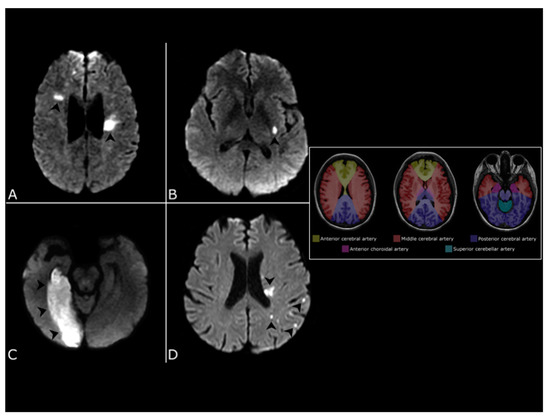

- Thaler, D.E.; Ruthazer, R.; Di Angelantonio, E.; Di Tullio, M.R.; Donovan, J.S.; Elkind, M.S.; Griffith, J.; Homma, S.; Jaigobin, C.; Mas, J.-L.; et al. Neuroimaging Findings in Cryptogenic Stroke Patients With and Without Patent Foramen Ovale. Stroke 2013, 44, 675–680. [Google Scholar] [CrossRef] [PubMed] [Green Version]

- Chung, J.; Park, S.H.; Kim, N.; Kim, W.; Park, J.H.; Ko, Y.; Yang, M.H.; Jang, M.S.; Han, M.; Jung, C.; et al. Trial of ORG 10172 in Acute Stroke Treatment (TOAST) Classification and Vascular Territory of Ischemic Stroke Lesions Diagnosed by Diffusion-Weighted Imaging. J. Am. Heart Assoc. 2014, 3. [Google Scholar] [CrossRef] [Green Version]

- Kim, B.J.; Sohn, H.; Sun, B.J.; Song, J.-K.; Kang, D.-W.; Kim, J.S.; Kwon, S.U. Imaging Characteristics of Ischemic Strokes Related to Patent Foramen Ovale. Stroke 2013, 44, 3350–3356. [Google Scholar] [CrossRef] [Green Version]